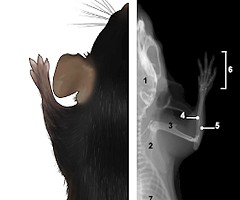

Publicado el primer Atlas de radiología del ratón

27 March 2021 -